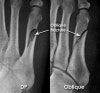

발의 AP view, lateral view, oblique X-ray 촬영을 실시합니다.

X-ray : 중족골 골절(Metatarsal shaft fracture)